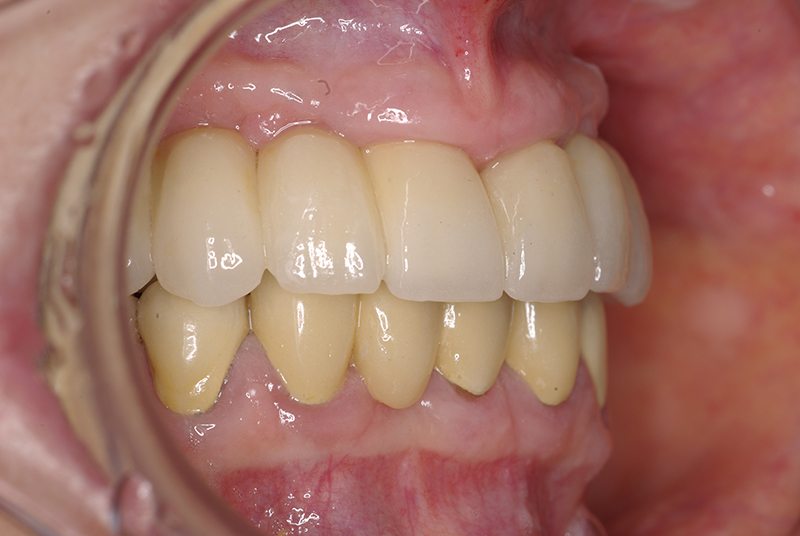

Utilizamos a tecnologia CAD CAM, um sistema avançado que possibilita a confecção precisa das próteses dentárias diretamente sobre os implantes. Esse método inovador garante um ajuste perfeito, um resultado estético superior e proporciona muito mais conforto e durabilidade. Com o CAD CAM, nossos pacientes contam com um processo mais rápido e previsível para alcançar o sorriso desejado.